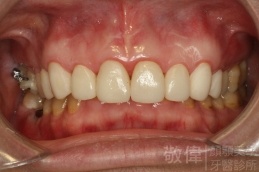

| 8 | 前牙美容 | 快速矯正之美容晶瓷貼片及晶鑽瓷冠 | ||